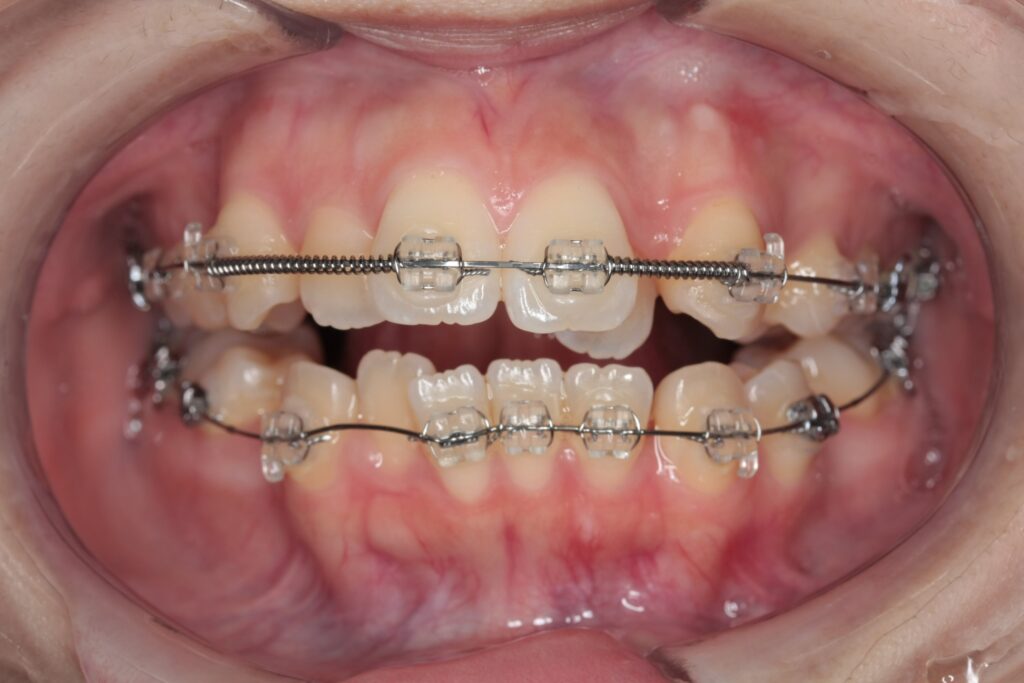

固定式矯正(ワイヤー矯正)

歯をしっかり動かす必要がある場合に選択する方法です。

頭部エックス線規格写真(セファロ)や口腔内スキャンをもとに、歯の角度、顎のバランス、噛み合わせの関係を細かく確認しながら治療計画を立てます。治療後の評価にも力を入れ、仕上がりや安定性を丁寧に確認します。